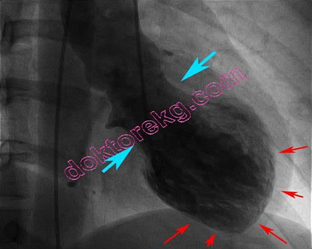

Kırık kalp sendromu, tıp diliyle takotsubo kardiyomiyopatisi. Yoğun stres yaşanan bir olayla birlikte kabaca sol karıncığın kasılmasının zayıflaması olarak tarif edebiliriz. Ancak bu durum çoğunlukla geçicidir. İlk kez 1990 yılında Japonya’da tanımlandı. Kalbin bu sıradaki görüntüsü japon balıkçıların ahtapot yakalamada kullandığı ağa (takotsubo) benzer ve ismi buradan gelir (Ceyhan ve Turgut, 2010).

Kalp krizi sanılarak hastaneye başvuran hastaların %1-2’si (her 50-100 kişiden biri) kırık kalp sendromu tanısı alır. Bu tanıyı kalp krizinden ayırmak güç olabilir. Ekokardiyografi (EKG) ve kan testlerinde sonuçlar birbiriyle örtüşse de asıl ayırıcı tanı koroner anjiyografi ve EKG ile konur. Kalp krizinde kalbi besleyen koroner damarlarda tıkanıklık görülürken kırık kalp sendromunda tıkanıklık yoktur. Anjiyografi ile damar tıkanıklığı olup olmadığı tespit edilir. Kırık kalp sendromunda kalp sol karıncığın üst kısmı balonlaşırken tabana yakın kısımlar normal kasılma görünümünü alır. Takotsubo isminin çıkış kaynağı da bu balonlaşmış görüntüdür. EKG’de de balonlaşmış görüntü tespit edilerek tanı konmuş olur. Kalp krizinde kasta balonlaşma görülmez (Sağlıkta Yenilikler, 2021).